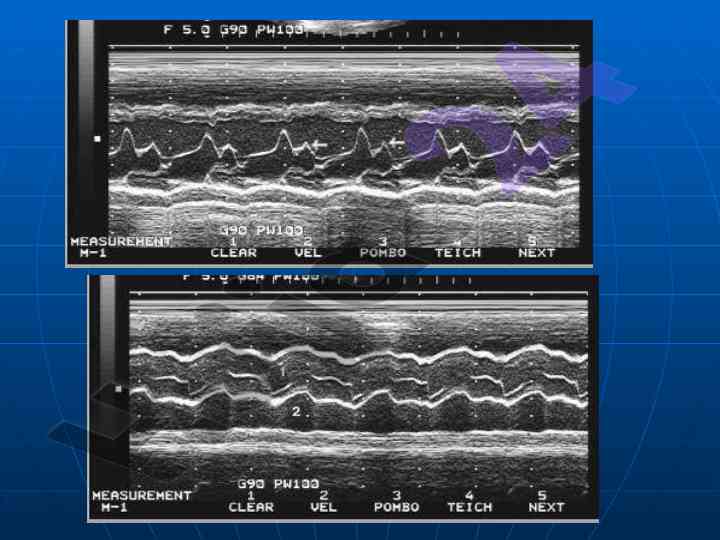

Ushbu maqolada yurak va qon-tomir kasalliklarining nurlanish tashxisi bo'yicha ma'lumotlar keltiriladi. U echokardiofragiya va angiografiya usullarini o'z ichiga oladi. Maqola universitetning tibbiy fakultet talabalariga yo'naltirilgan.